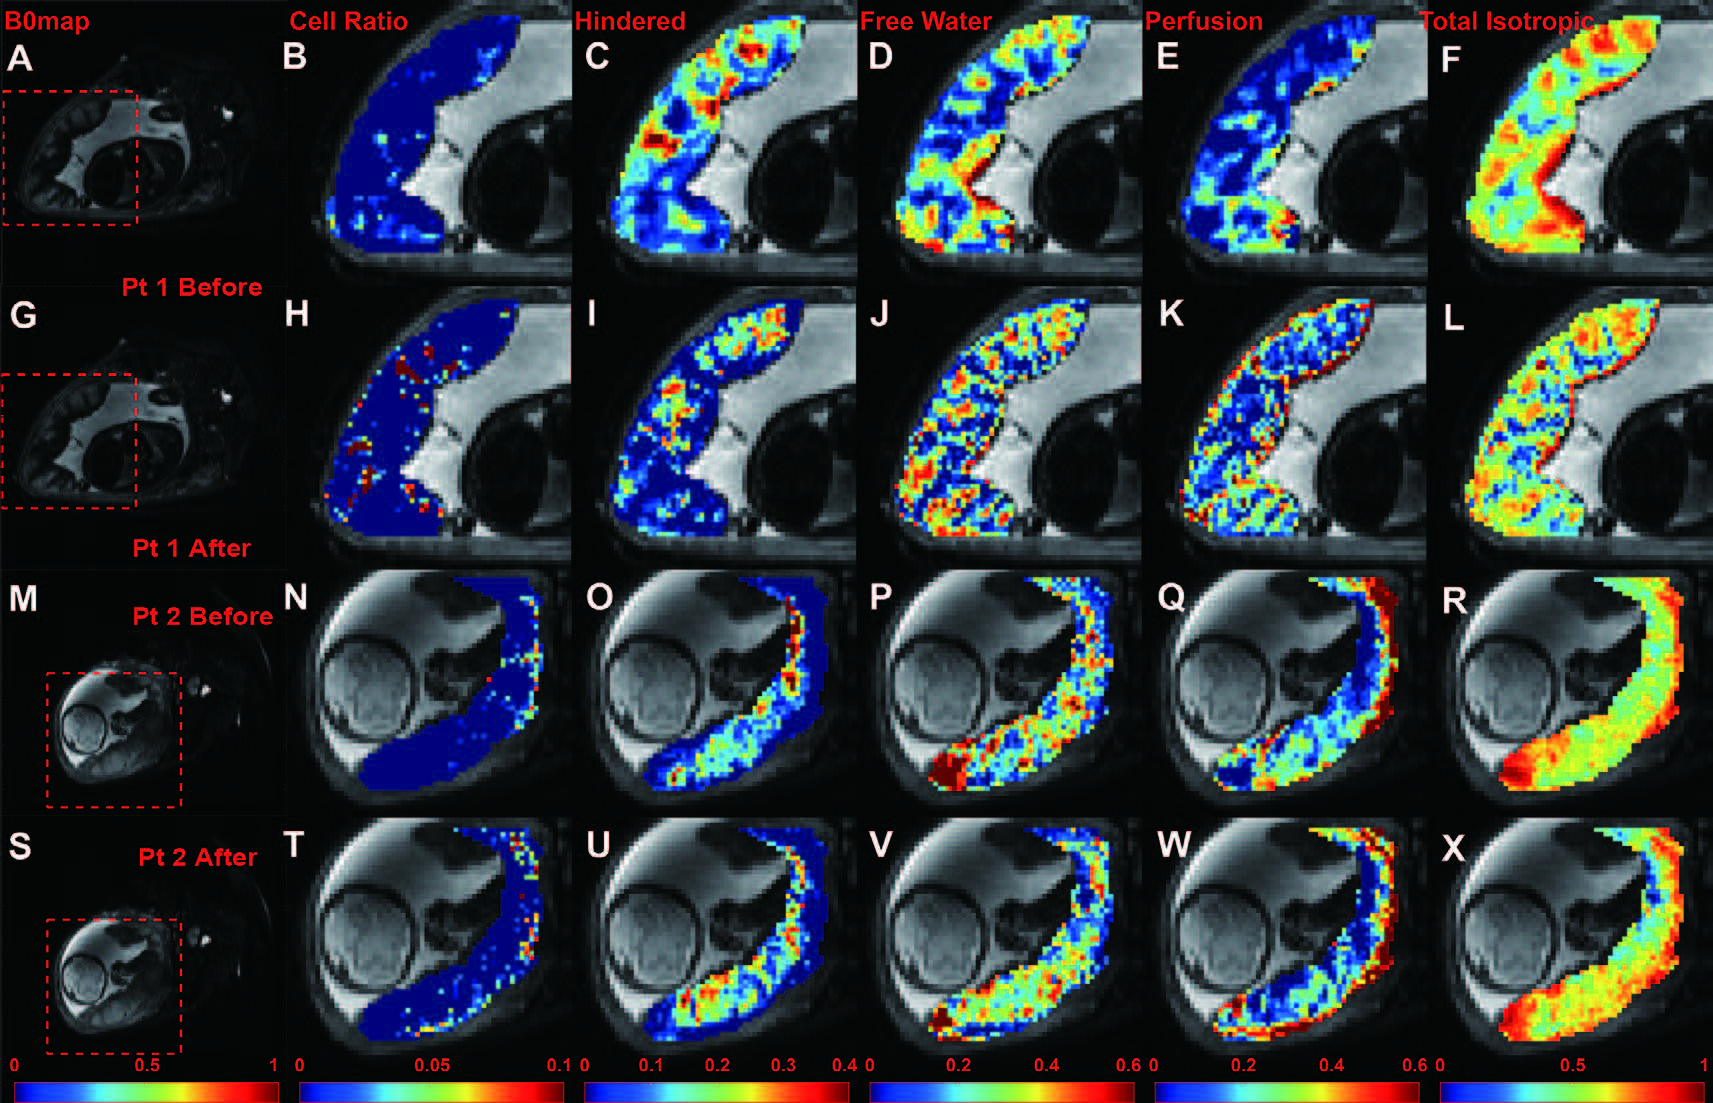

After registration, DBSI was employed to analyze the registered DWI images and extract the parameters describing sub-voxel information. Maps of cellularity ratio, hindered diffusion ratio, free diffusion ratio, perfusion ratio and total isotropic component ratio are presented in Figure 4.

Figure 4: Full DBSI results before and after registration, from two patients. First row (A–F): b0 map, cellularity ratio, hindered diffusion ratio, free diffusion ratio, perfusion ratio and total ratio of isotropic components from Pt 1 before registration. Second row (G–L): Pt 1 results after registration. Third row (M–R): Pt 2 results before registration. Fourth row (S-X): Pt 2 results after registration. Pt 1: a patient with pregnancy with no detected abnormality, MRI at 35 weeks GA; Pt 2: a patient diagnosed with incidental septal cyst and infarct, MRI at 33 weeks GA. MRI: magnetic resonance imaging; GA: gestational age.

In our theory: (1) cellularity represents immune cell infiltration (Figure 4B, H, N, and T); (2) hindered diffusion ratio represent the diffusion in matured terminal villa with rich membrane in healthy cases and local tissue edema in pathological cases(Figure 4C, I, O, and U); (3) free diffusion ratio represents less matured villa(Figure 4D, J, P, and V); (4): perfusion ratio represent fast blood flow in the vessel (Figure 4E, K, Q, and W); (5): total isotropic component ratio (Figure 4F, L, R, and X) is the summation of (1) to (4).

We presented and compared the DBSI derived maps of the placentas before and after registration. After registration, patterns from all DBSI maps changed remarkably. We saw cellularity increase in both intensities and areas. And the cellularity is more evenly distributed in placenta. In Patient 1, the free diffusion ratio map reveals clearer pattern of cotyledons after registration. Also, we observed increased perfusion component near the basal plate, which is consistent with the physiology and previous publication.[15]